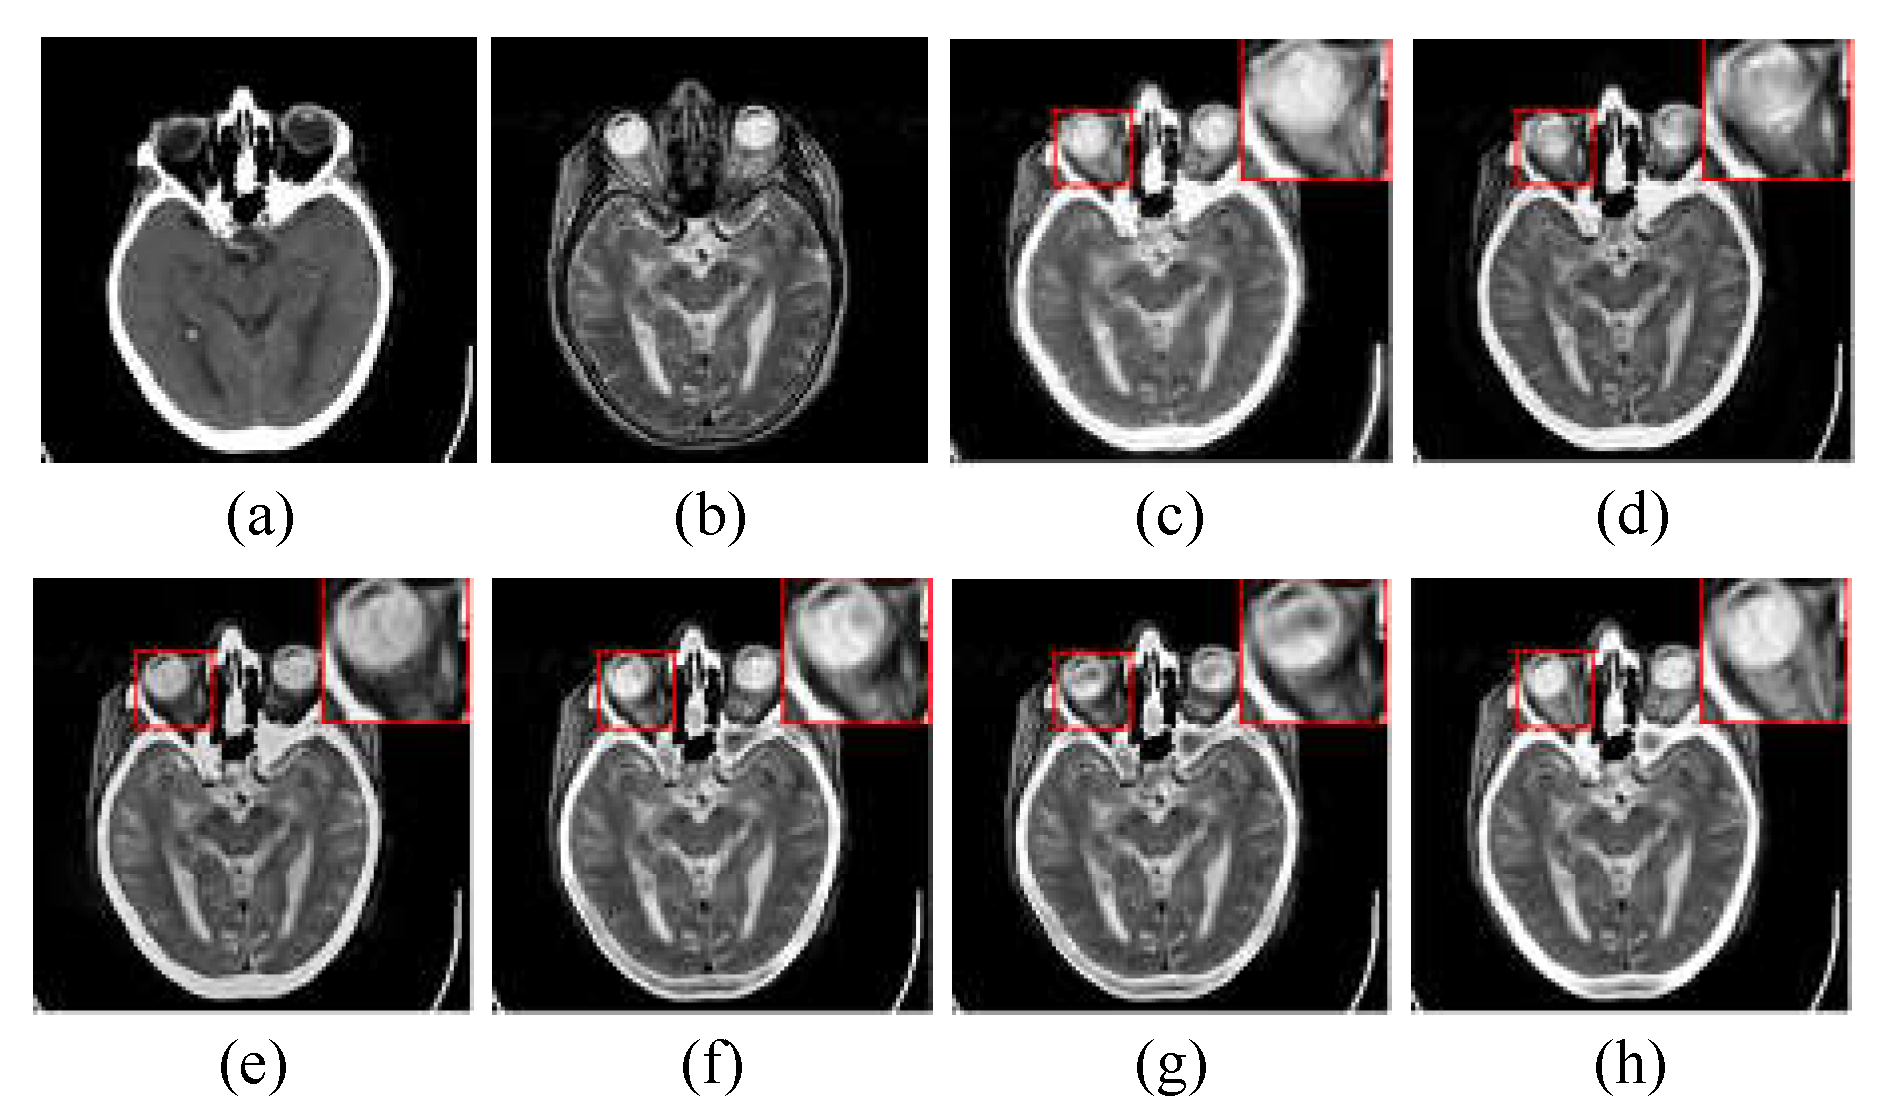

In the experiments of multimodal medical image fusion, CT and MRI image fusion is the most common, since the information provided by CT and MRI images can create a good supplement, while the multimodal combination category can be expanded to other types with the fusion method of this paper. Figure 4 shows the randomly selected nine groups of multimodal medical fused image in subjective visual experiments, and the first three groups belongs to “Acute stroke”, the second three groups belongs to “Hypertensive encephalopathy”, and the last three groups belongs to “Multiple embolic infarctions”. To better intuitively reflect the superiority of the proposed method, one group of typical fusion example is selected from each of the three WBAMI categories to conduct a detail analysis of the amplification of representative regions, as shown in Figure 5,Figure 6Figure 7, respectively.

The CT/MR-T2 fusion results and the red box selections of the proposed method and competitors are shown in Figure 7. It is clear that artifacts appear when using LRD method (see (c) in Figure 7). NSST-MSMG-PCNN, CSMCA, l1-norm and SSSF have lost luminance, and all of them are in the situation of partial details reduction (see (d), (e), (f) and (g) in Figure 7). In contrast, the proposed method is obviously superior to competitors in luminance and detail information retention (see (h) in Figure 7).

Figure 7. The CT/MR-T2 image pair from “Multiple embolic infarctions” category and the corresponding fusion results with different methods: (a) and (b) are the CT image and MR-T2 image, respectively; (c) is the fusion result of LRD; (d) is the fusion result of NSST-MSMG-PCNN; (e) is the fusion result of CSMCA; (f) is the fusion result of l1-norm; (g) is the fusion result of SSSF; (h) is the fusion result of the proposed method.